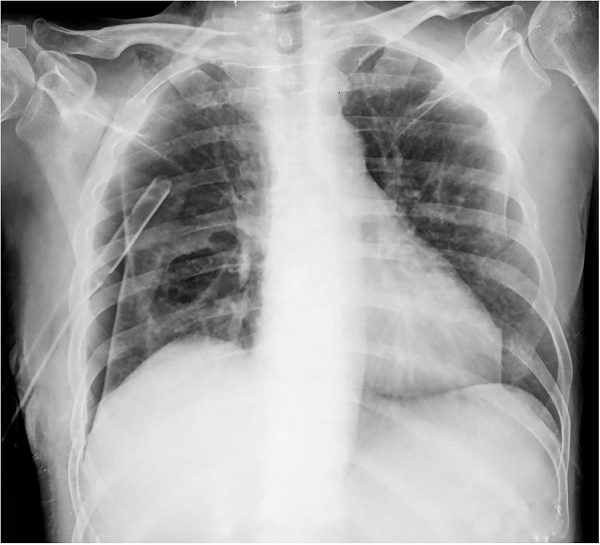

On admission to the Infectious Diseases Department, the patient was pale, disoriented, had tachycardia, decreased breath sounds at the base of the right hemithorax, which had a thoracic drainage tube. A new chest x-ray revealed right pneumothorax and an ovoid, homogeneous opacity without any air-fluid level in the right lower lung lobe, and the presence of thoracic drainage (Figure 2). A non-contrast chest computed tomography was performed, revealing the pneumothorax with irregular cavitation in the right hemithorax.

The cavitation measured 10.0 × 7.5 × 5.0 cm, had thickened walls, and was located in the pleuropulmonary interface of the posterior margin of the right lower lobe. Its interior showed tissue bands indicating permeation and fluid collection consistent with an abscessed/necrotizing lung lesion in contact with the pleural space. Centrilobular ground-glass opacities, predominantly in the central regions of the left lung, were also visualized, probably representing a non-specific, inflammatory/infectious process (Figures 33B).